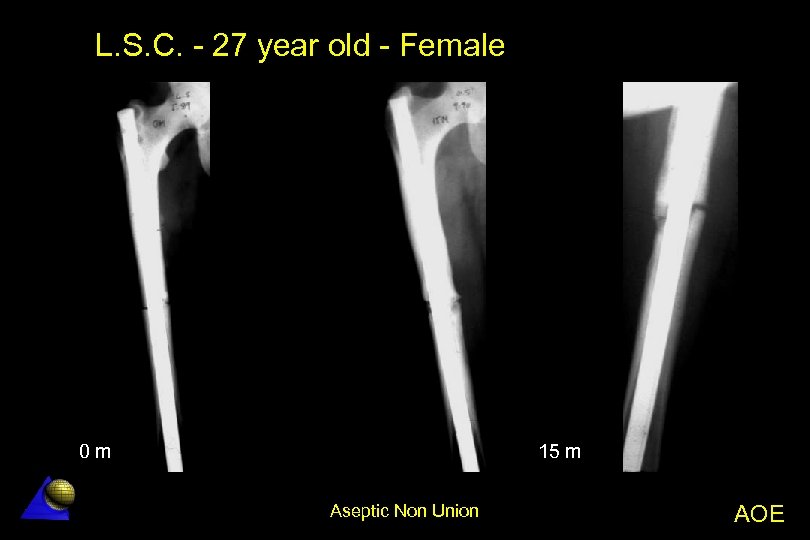

L. S. C. - 27 year old - Female Femoral non-union - 5. 89 l Right femur transverse fracture â Primary reamed IM nailing No callus formation at 15 months l Nail failure at 16 months l Treatment l â Nail removal without opening the fracture site â New reamed thicker nailing l Bone healing in 2 months Aseptic Non Union AOE

L. S. C. - 27 year old - Female 0 m 15 m Aseptic Non Union AOE

L. S. C. - 27 year old - Female 16 m 24 m Aseptic Non Union AOE